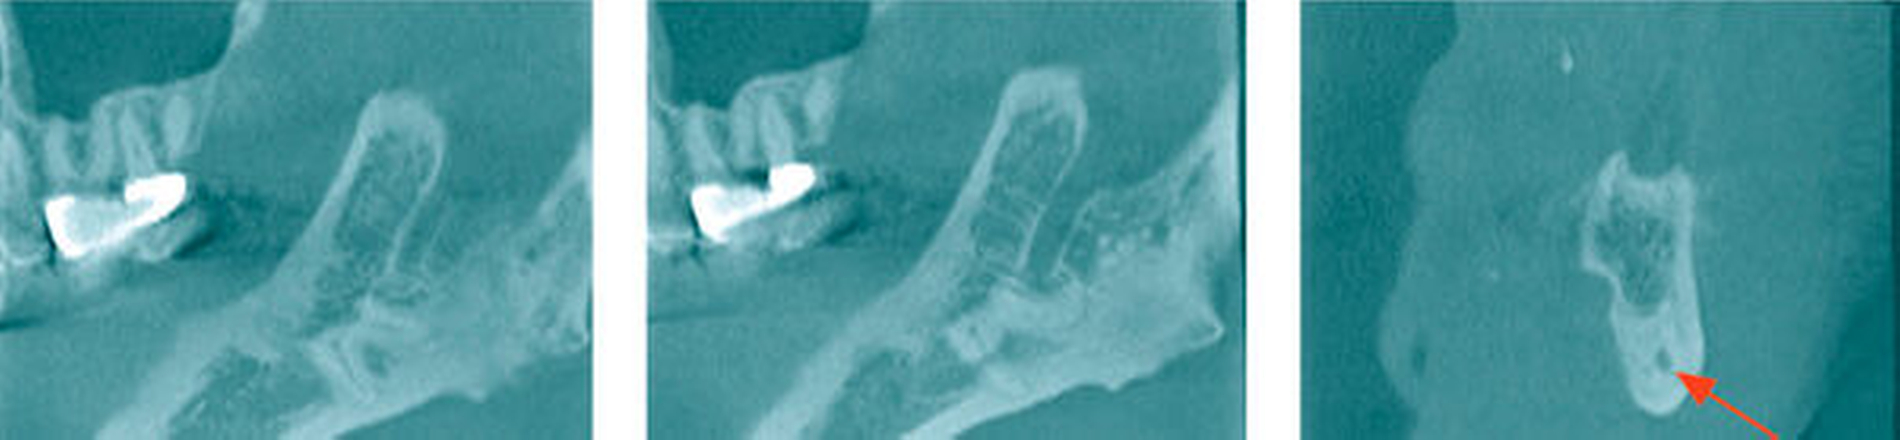

Nach Abwägung der Risiken (Schädigung des N. alveolaris inferior, hoher Knochensubstanzverlust im Unterkiefer) war damals gemeinsam mit dem Patienten entschieden worden, eine Koronektomie am Zahn 38 durchzuführen. Die erste Verlaufskontrolle erfolgte im März 2015, bei der in der Panoramaschichtaufnahme eine Reossifikation nachgewiesen werden konnte (Abbildung 8). 2017 konnte röntgenologisch koronar der Radices 38 eine suffiziente Knochenneubildung festgestellt werden (Abbildung 8). Der Patient war beschwerdefrei, die Wundverhältnisse waren vollkommen reizlos und ohne Schwellung.

Aktuell wird bei ihm die operative Entfernung des Zahnes 28 geplant, der nun symptomatisch ist. Die Verlaufskontrolle nach der Koronektomie am Zahn 38 vor sieben Jahren zeigte auf der zur Planung der Entfernung von 28 angefertigten Aufnahme einen unauffälligen Befund mit deutlichem Nachweis einer Reossifikation im ehemaligen Kronenbereich (Abbildung 9). Der Patient gab an, dass er mit der Entscheidung damals zufrieden sei und er keinerlei Beschwerden in dieser Region habe.